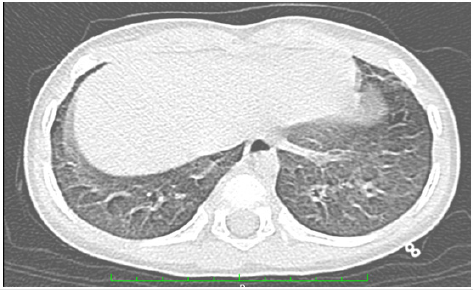

An echocardiogram showed a structurally normal heart, with no data of pulmonary hypertension. The treatment included ceftriaxone for seven days, clarithromycin for ten days, and nitazoxanide for five days. Treatment with methylprednisolone was given for five days, and treatment with prednisone (1 mg/kg/ day) was continued for seven days. Oxygen delivery devices were gradually scaled back until ambient air saturations of 92% to 98% were achieved. A thorax CT scan was requested since the condition of the patient allowed it.

Tomography

Axial Cut (Figure 4)

Single-phase tomography with pulmonary parenchyma window. Ground glass pattern is observed towards the superior lobes, showing area of healthy parenchyma toward the anterior segment of the right superior lobe.